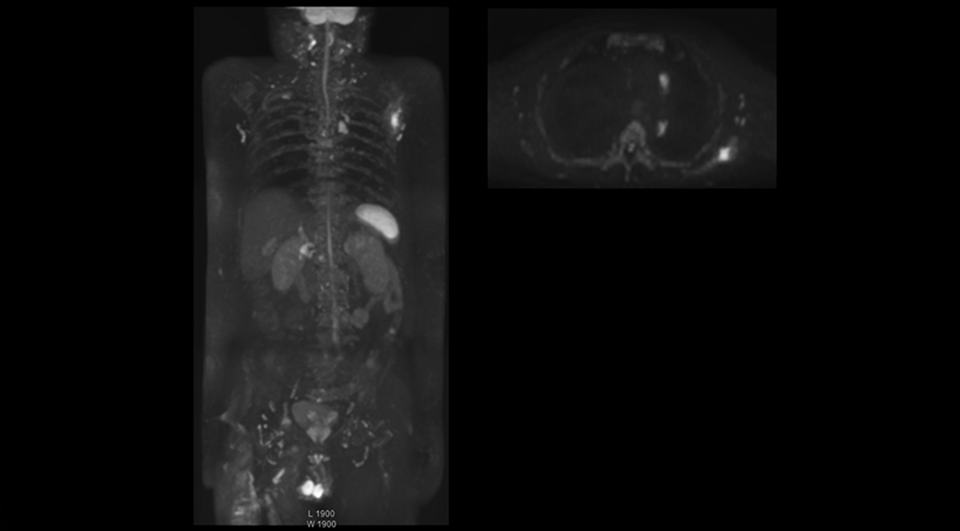

“The DWIBS sequence’s value in oncology cases is due to the high contrast it creates between lesions and surrounding tissue. Whole body DWI is requested by physicians who need to clarify TNM staging or determine therapeutic strategies, oncologists in need of diagnosis or follow-up scans, surgeons who need to see the presence of distant lesions that are sometimes difficult to detect by CT before surgery, and urologists for the evaluation of bone lesions, and the effect of chemotherapy and radiotherapy.”

“Switching to coronal DWIBS – rather than axial – further shortens scan time,” says Mr. Naka. “Important is that a dS SENSE factor of 5 shortens exam time while high image quality can be maintained, thanks to Ingenia’s dStream architecture.” He adds that the coronal orientation also avoids artifacts that are specific to combining axial images.

“When we use a coronal DWIBS acquisition, we can perform a full whole body examination, including other required sequences, within 30 minutes,” he says.

After implementing the improved whole body protocol, the radiology team initially did not see a large increase in referrals, although Dr. Nobusawa saw clinical cases where the DWIBS images provided him valuable information for diagnosis. This is why Dr. Nobusawa and Mr. Naka started to actively educate referring physicians about the value of whole body DWIBS. They organized several presentations for physicians in the hospital, where they explained how DWIBS can be of value in oncology patients. The information it provides can be useful for physicians when staging cancer, as well as when determining or adjusting treatment strategy. Mr. Naka remembers some cases where DWIBS provided remarkable information. “In one example, DWIBS visualized bone lesions that could not be seen on PET or SPECT. In another case we had found a bone lesion when a normal L-spine scan for narrowing of the disk space was done. One extra DWIBS scan (2 stations, 8 minutes) demonstrated a lesion that later was confirmed to be the primary region of cancer.”